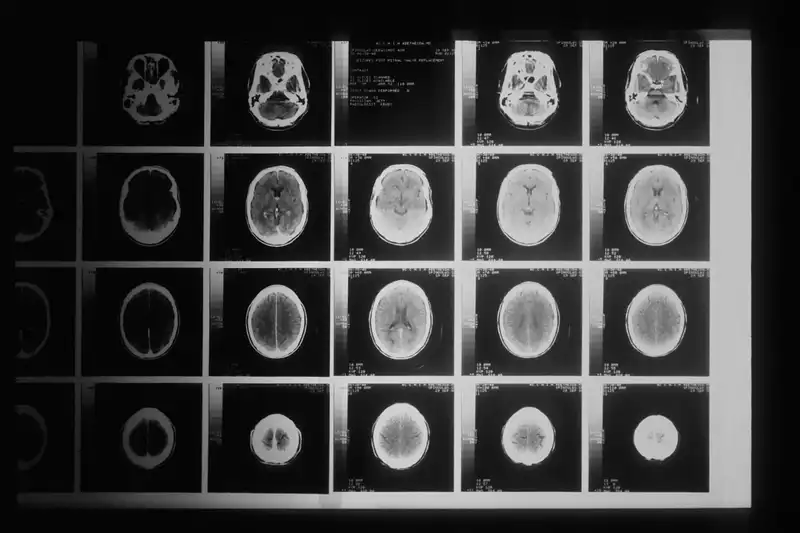

Peu à peu, les résultats deviennent surprenants : les examens montrent une réduction progressive de la tumeur, jusqu’à sa disparition complète. Les médecins, d’abord prudents, n’en reviennent pas. C’est la première fois qu’un tel phénomène est observé chez un enfant atteint d’un DIPG.

Douze ans après le début de sa maladie, les images cérébrales de Lucas sont claires : aucune trace de tumeur. Depuis plus d’un an, il ne suit plus aucun traitement, et son état reste stable. Les chercheurs du centre Gustave-Roussy pensent que cette guérison spectaculaire pourrait être liée à une mutation génétique rare dans les cellules tumorales de Lucas, rendant la tumeur particulièrement sensible au médicament expérimental.